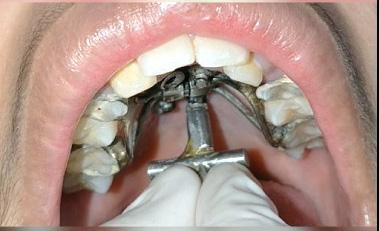

To prevent a disto-lingual moment (rotation) of the maxillary cuspids we attached PC from the lingual button on the cuspids to the framework on the hyrax. The anterior portion of the Hyrax was cut off and the remaining portion served as a TP arch for posterior anchorage. At this point, we were 25 months into treatment (Figure 9-A, B, C, D). The hyrax was removed after 30 months of treatment.

Figure 8A: TADs in situ, frontal view 8B: TAD in situ, right lateral view 8C: TAD in situ, left lateral view 8D: Power arms Figure 9A: Maxilla, occlusal view 9B: Maxilla, occlusal view 9C: Maxilla, occlusal view Figure 9D: After the removal of the Hyrax, occlusal view Figure 10A: Center bend “V” pointing gingivally Figure 10B: OCS between the cuspids and the central incisors Figure 10C: Composite build-ups on the mandibular first molars Figure 10D: Adrian “U” bend spring